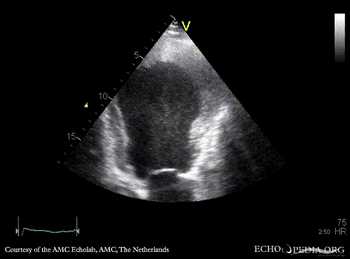

E00217.gif E00218.gif

PLAX: dilated left ventricle with poor function PSAX: dilated left ventricle with poor function, spontaneous echo contrast